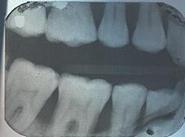

Radiografii

Parodontite moderate

dintii par alungiti datorita retractiei gingivale

pot apare abcese parodontale

halena

mobilitate dentara si diastemizare patologica

pungi parodontale de 4-6 mm

resorbtie osoasa